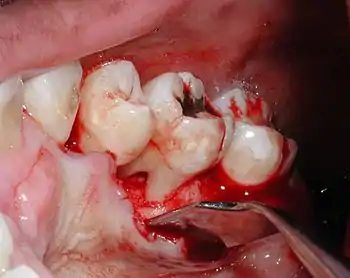

Diagnosis

Nabers probe is used to check for furcation involvement clinically. Recently, cone beam computerised technology (CBCT) has also be used to detect furcation.[5] Periapical and interproximal intraoral radiographs can help diagnosing and locating the furcation.

Only multirooted teeth have furcation. Therefore, upper first premolar, maxillary and mandibular molars may be involved. Upper premolars have one buccal and one palatal root. Maxillary molars have three roots, a mesio-buccal root, disto-buccal root and a palatal root. Mandibular molars have one mesial and one distal root, and so.